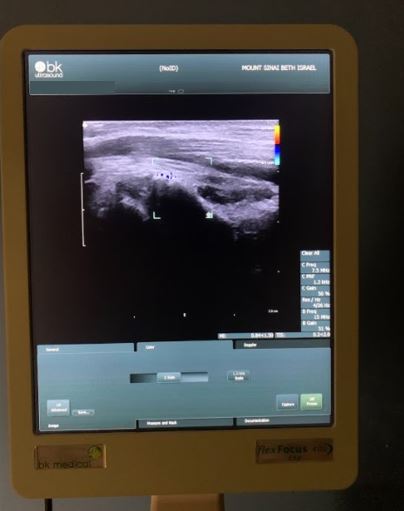

The emergence of CDU within the field of ABBR provided surgeons with the capability to identify a perforator’s precise location, course, and caliber (Figure 2). Unlike its predecessor, CDU can distinguish perforator vessel branches from their main axial trunks by using similar acoustic signaling but with superior association with large caliber and blood flow and other favorable hemodynamic characteristics.8 Given its stronger frequency signals, CDU is better able to identify small-diameter vessels (ie, as small as 0.2 mm).7,13,14 If positioned correctly, the perforator’s full course can be mapped even if it penetrates muscle or fascia.7,13,16 Thus, branching networks of a main axial vessel can be better characterized, giving the surgeon a greater ability to distinguish the signal of a suitable perforator from other vessels more reliably.15